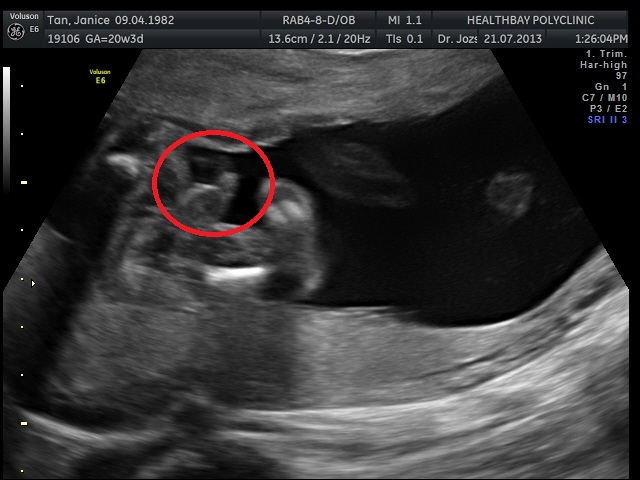

Visit #4 to see Dr Jozsa

Weight Check: 60.7kg

That's 1.4kg in 4 weeks!

Though the little bean is 343grams...

And we have a dancing baby ready to PARTY!

The scan is all good...

The brain is all in place, and so is the diaphram, kidneys, heart, gall bladder, liver, fingers and toe.

And he's definitely a boy.